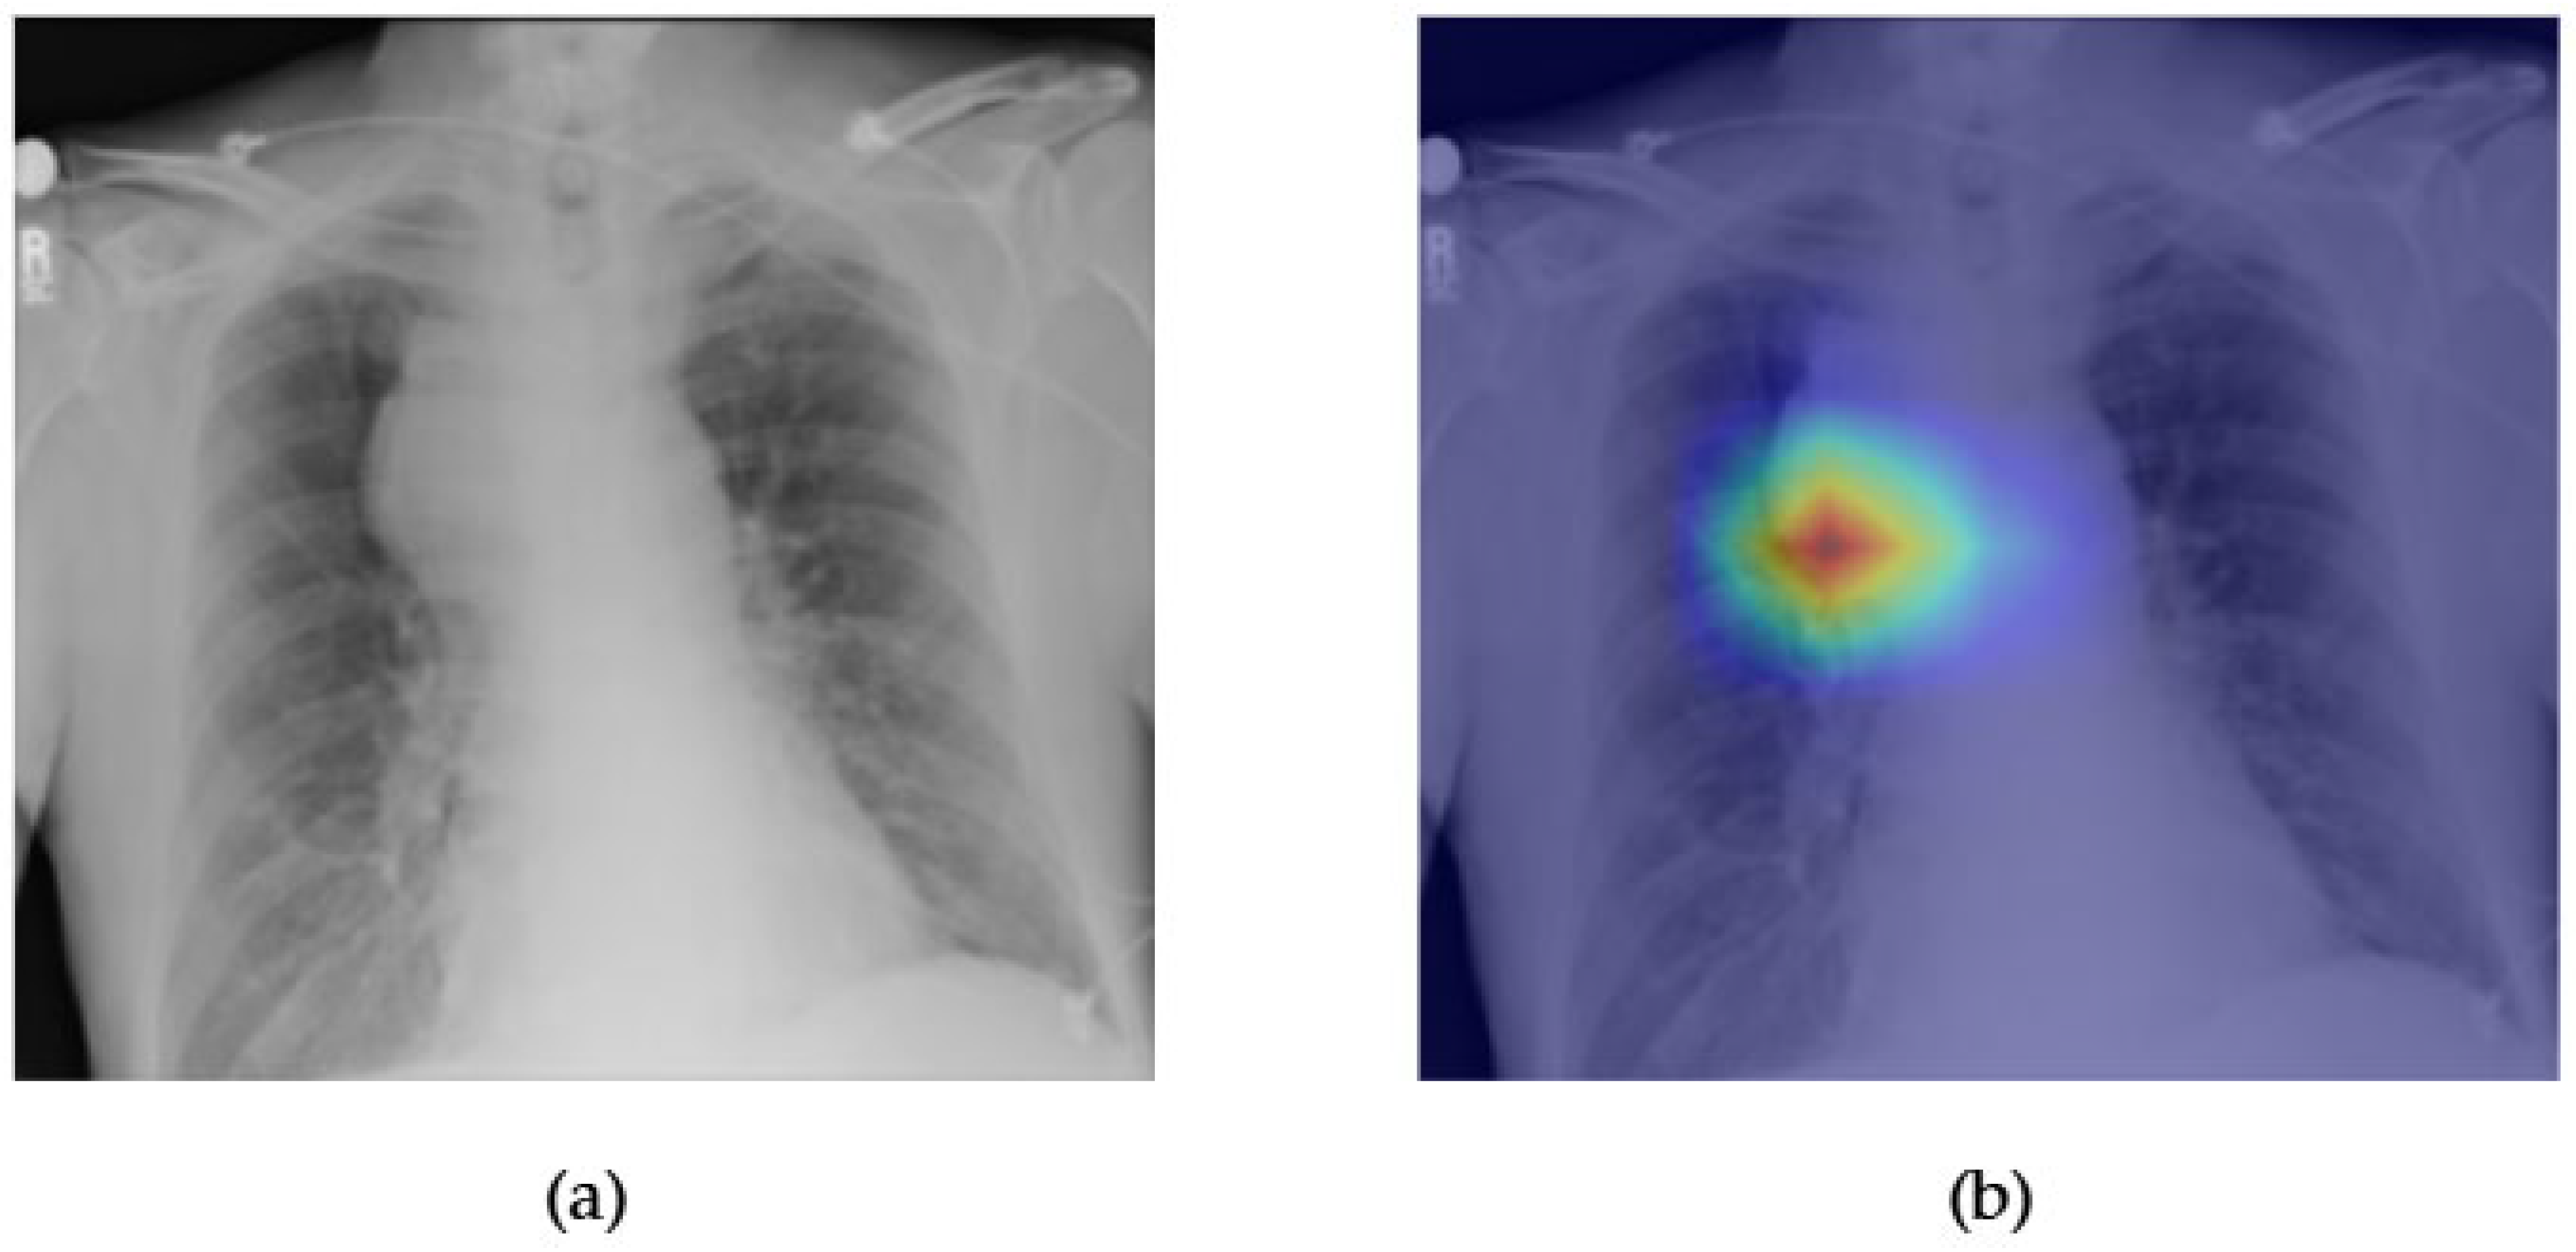

- Although our Grad-CAM-based explainability provides useful localization cues, it is inherently limited by its post hoc nature and reliance on gradient flow from the final convolutional layers. Future research could incorporate advanced interpretability techniques such as Layer-wise Relevance Propagation (LRP), Integrated Gradients, or attention rollouts in Transformers, which may offer a more complete understanding of model reasoning.